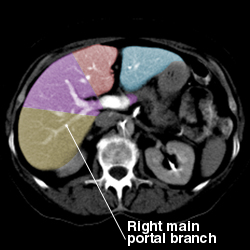

Liver anatomy

Portal Vein:

Segmental Anatomy of Liver